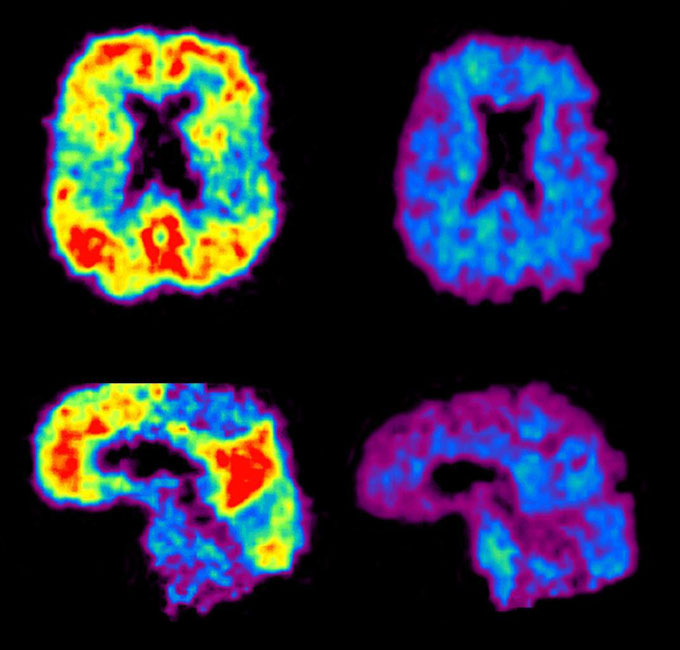

Alzheimer’s blood tests are getting better, but still have a ways to go

Alzheimer’s disease is hard to diagnose. But proteins in the blood might provide clarity. A series of recent findings, presented at the annual Alzheimer’s Association International Conference in Philadelphia and in research papers, raise the possibility of a simple blood draw to help doctors figure out if a person’s cognitive problems are caused by Alzheimer’s … Read more